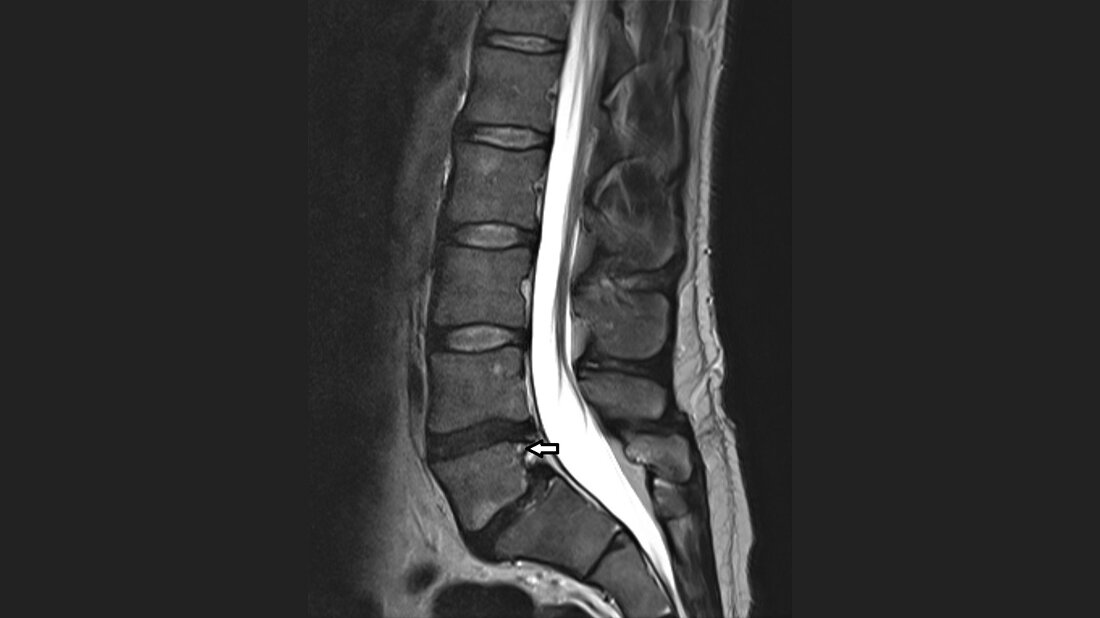

Die Reduktion des anteroposterioren Wirbeldurchmessers lumbal ist relativ selten und stellt in den meisten Fällen eine anatomische Variante dar. Bei degenerativ bedingter Spondylolisthese kann die Formänderung sogar zu einer Reduktion der klinischen Symptomatik führen.

The reduction of anteroposterior diameter of lumbar vertebral body is rare. It is an anatomical variant. In case of degenerative spondylolisthesis the data suggest that reduction of slipped vertebral body could be effective to relieve clinical symptoms.